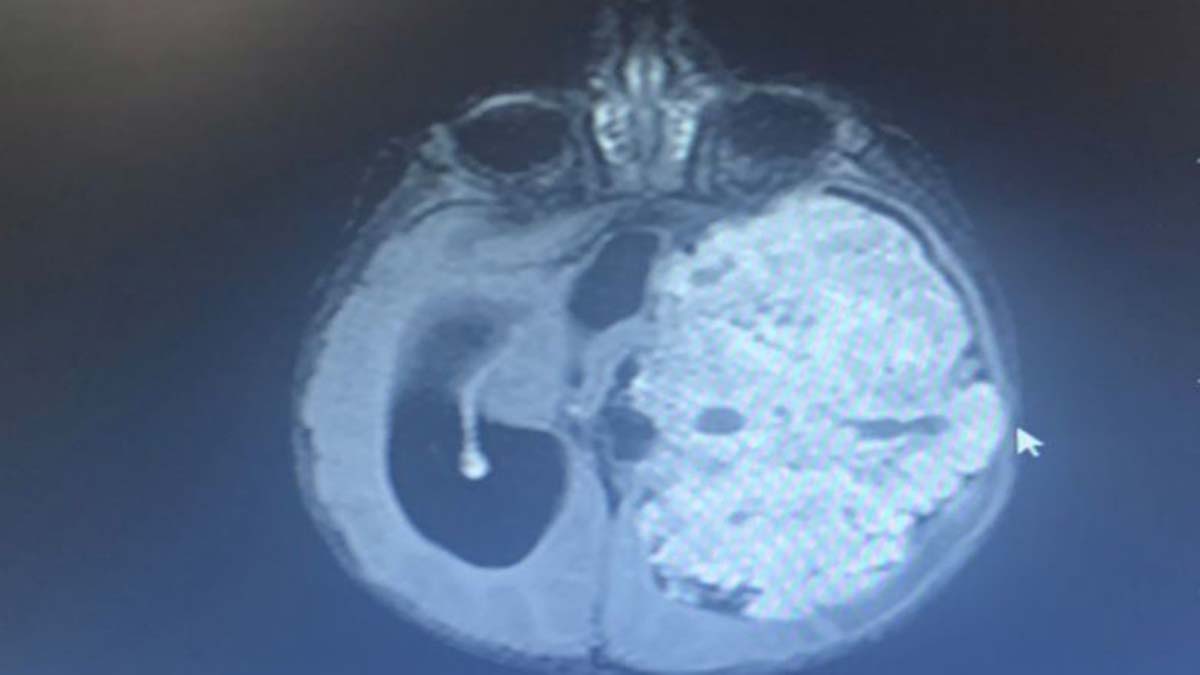

Şanlıurfa’da 1,5 yıllık evli Saniye ve Yunus Kılıç, 3 aylık bebekleri Mehmet Asaf Kılıç’ın kafasının sol tarafında oluşan şişliği fark edince Şanlıurfa Eğitim ve Araştırma Hastanesi’ne başvurdu. Beyninde kitle olduğu belirlenen Asaf bebek, Ankara Sağlık Bilimleri Üniversitesi Gülhane Eğitim ve Araştırma Hastanesi’ne sevk edildi. Asaf’ın çekilen MR’ında beynin sol tarafının tamamen tümör ile kaplı olduğu tespit edildi. Asaf bebeğin ameliyat edilmesi kararlaştırıldı ve 9 saat süren operasyonla beynindeki tümör temizlendi. Asaf bebek, tedavi sürecinin ardından sağlığına kavuştu.

Mehmet Asaf’ın doktoru Beyin ve Sinir Cerrahisi Uzmanı Doç. Dr. Cahit Kural, Asaf’ı ilk gördüklerinde yolunda gitmeyen bir şeyler olduğunu hissetiklerini belirterek, “Acil olarak MR çektirdik. Beyin MR’ında beynin sol tarafını tamamen dolduran, sağ tarafına bası yapan devasa bir kitle vardı. Zaman kaybetmeden hemen ameliyata aldık. Ameliyatta tümörün tamamını çıkardık. Bu büyüklükte tümörler çok nadir görülür. Beynin yarısını dolduran bir tümördü. Hastamız çok küçük, tümör çok büyük, riskli bir ameliyattı. 8-9 saat süren bir ameliyatın ardından iyileşti, sağlıklı şekilde evine gönderiyoruz” dedi.

Çıkarılan örnekleri ileri inceleme için patoloji bölümüne gönderdiklerini belirten Kural, “‘Atipik koroid pleksus papillomu’ tanısı geldi. Bu çok nadir görülen bir tümör. Beyni bu kadar dolduran tümör görmek, çoğu zaman mümkün değil. Tümörün hepsini çıkardığımız için kemoterapi düşünmüyoruz” diye konuştu.